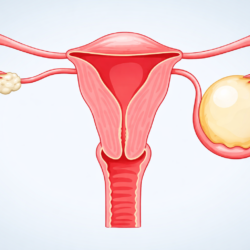

Die vollständige Entfernung der Gebärmutter, medizinisch als Hysterektomie bezeichnet, ist eine der wichtigen chirurgischen Methoden in der Behandlung gynäkologischer Erkrankungen. Dieser Eingriff kann aus verschiedenen Gründen erforderlich sein, wie z. B. bei großen Myomen, nicht kontrollierbaren abnormalen Blutungen, einigen gynäkologischen Krebserkrankungen, chronischen Schmerzzuständen oder einem fortgeschrittenen Gebärmuttervorfall.